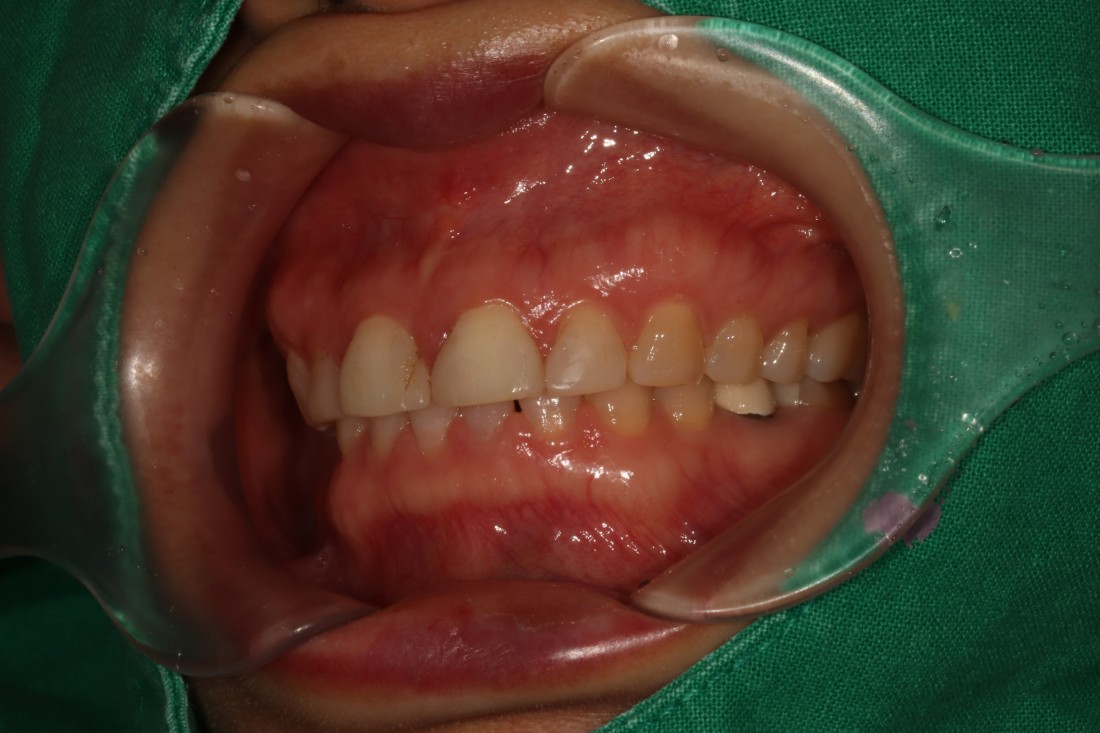

대표원장이 직접 전/후 사진을

비교하며 포스팅 해오고 있는

광주 무삭제 라미네이트

실제 사례는 위의 링크를

클릭하시면 보실 수 있습니다.

압도적인 실제 사례 케이스 건수로

증명하는 광주 무삭제 라미네이트 치과의

실력입니다.